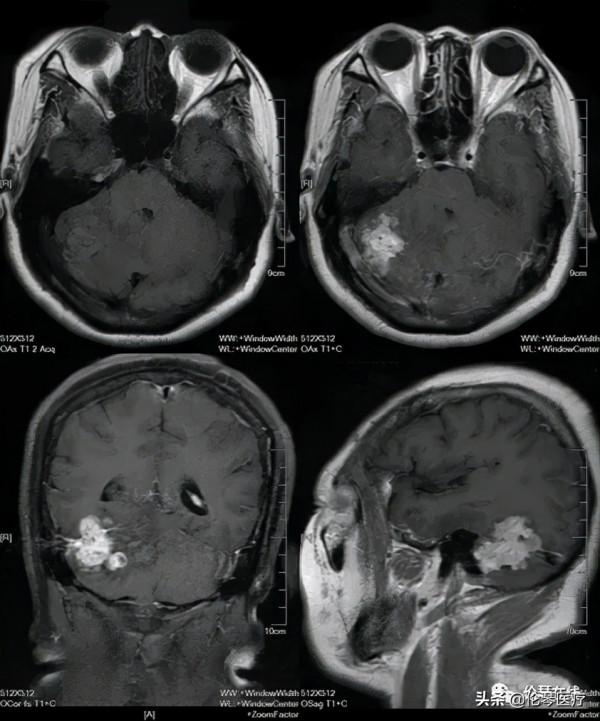

關鍵影象: